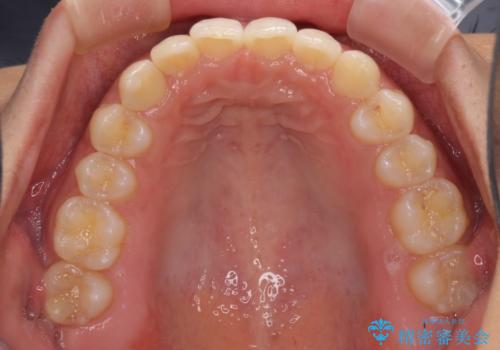

- 深い咬み合わせ(ディープバイト)と前歯のデコボコを気にして来院された患者様です。

インビザラインによる上下歯列の側方拡大と後方移動、IPR(歯と歯の間を削る)にるスペースの獲得により、デコボコとディープバイトを改善することとしました。

1日22時間の装着時間をしっかり守ってくださったので、予定通り1年で治療を終えることができました。

ディープバイトによる食いしばり癖も解消され、患者様には大変満足していただきました。